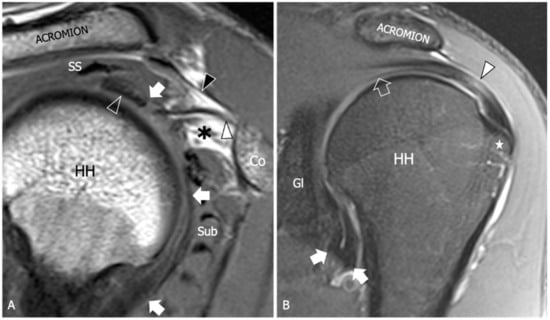

Figure 2.

Glenohumeral joint capsule, normal MRI findings. (A) Sagittal tSE T1-weighted MRI image shows the joint capsule (arrow) as a structure of intermediate signal located deep to the rotator cuff tendons. Note the intra-articular part of the long head of the biceps tendon (outlined arrowhead) running on the inner surface of the capsule. The coracohumeral ligament (white arrowhead) is demonstrated as a thin and low signal fibrillar structure running from the coracoid (Co) to the humeral head (HH). The subcoracoid fat triangle (asterisk) is a fat-filled space delimited by the coracohumeral ligament, the joint capsule, and the subscapularis (Sub) muscle. SS, supraspinatus muscle; black arrowhead, coracoacromial ligament. (B) Coronal tSE fat-suppressed T2-weighted MRI scan shows the inferior part of the joint capsule (arrow) as a low signal folding that delimits the axillary recess. Note the thin superior capsule (outlined arrow) located underneath the supraspinatus muscle and tendon (arrowhead). Gl, scapular glenoid; HH, humeral head; star, greater tuberosity.